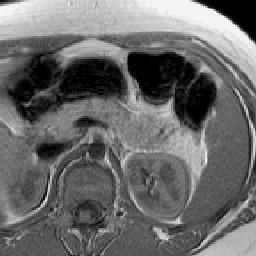

With the goal of obtaining the detailed and accurate segmentation outcome for complex and difficult objects, a number of deep learning approaches have been proposed recently [11, 20, 21, 12, 16]. Some of these models regularize deep learning output with the original image appearance that the image pixels sharing similar colors (or intensity values) probably come from the same object category. Conditional random field or CRF [20, 21] is proposed to handle this scenario. Other methods propose to learn more localized deep features. For instance, deep supervision is proposed in [12, 14], forcing all convolutional layers to learn effective and consistent low-level representations to capture local image features, e.g., edge and object boundary. Meanwhile, UNet architecture in [16] is presented to make full use of low-level convolutional feature maps by projecting them back to the original image size which delineates object boundaries with details. To combine virtues of both network design, we propose to adopt and build upon the previously proposed UNet [16] and holistically nested network (HNN) [12] in this paper due to their end-to-end trainable nature as well as excellent segmentation performances. As shown in Fig. 2, the output of UNet catches many details implying that the dedicated backward propagation combining convolutional layer features of multiple scales is helpful to accurate pancreas segmentation. However, the probability map of a well-trained UNet can still be blurring, along with false positive detections.

Delineating the pancreas boundary from its surrounding structures in CT/MRI imaging can be challenging due to its complex visual appearance and ambiguous outlines. For example, Fig. 2 displays a cross-section area of a pancreas in CT, where the pancreas shares similar intensity values with other soft tissues and its boundary is blurry where touching with abdominal organs. Strong existence of visual ambiguity for pancreas segmentation in CT (and MRI) imaging modalities demonstrate very different image statistics from the problem of semantic object segmentation in natural images. Direct transfer learning of natural image pre-trained CNNs to medical domain might be suboptimal. More specifically, when fine-tune an ImageNet pre-trained model [27] for pancreas segmentation, we observe that the training loss drops fast, indicating that the top CNN model layers can capture the hierarchical (conceptual) appearance representation of pancreas sufficiently. However, the magnitudes of gradients (back-propagated from the training error) decrease rapidly to leave the bottom CNN layers not well tuned. This situation becomes even worse when the gradient-vanishing problem occurs during model training. To alleviate this undesirable effect, we propose and exploit a new method to enable CNN that can be effectively trained from scratch, even with small-sized medical datasets.